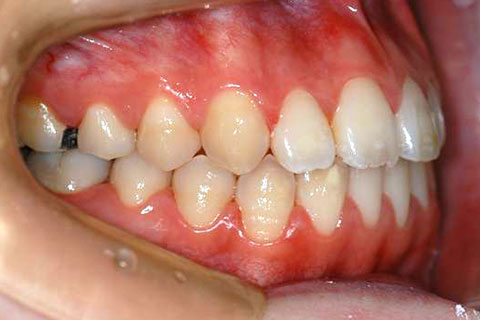

症例1

治療前

年齢・性別

23歳女性

治療期間

1年4ヶ月

抜歯

なし

治療費

80万(税込)

備考

マルチブラケットを用いた矯正治療

治療内容

前歯の開口を顎間ゴムにて改善

施術の副作用(リスク)

舌の癖や鼻疾患がある時は、後戻りを起こすことがあります。